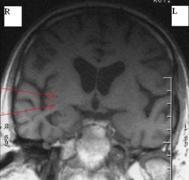

Examenul MRI cerebral efectuat peste doua saptamāni arata aceleasi zone milimetrice de hipointensitate īn T1 si hiperintensitate īn T2 īn substanta alba la nivelul lobulul temporal drept, imediat subcortical.

Examenul CT arata: focare milimetrice de hipodensitate spontana parietal si frontal drept īn vecinatatea coarnelor anterioare ale ventriculului drept. Sistemul ventricular este ectaziat, normal pozitionat. santurile corticale si vaile silviene sunt accentuate. Concluzii: Lacunarism cerebral. Atrofie cerebrala.